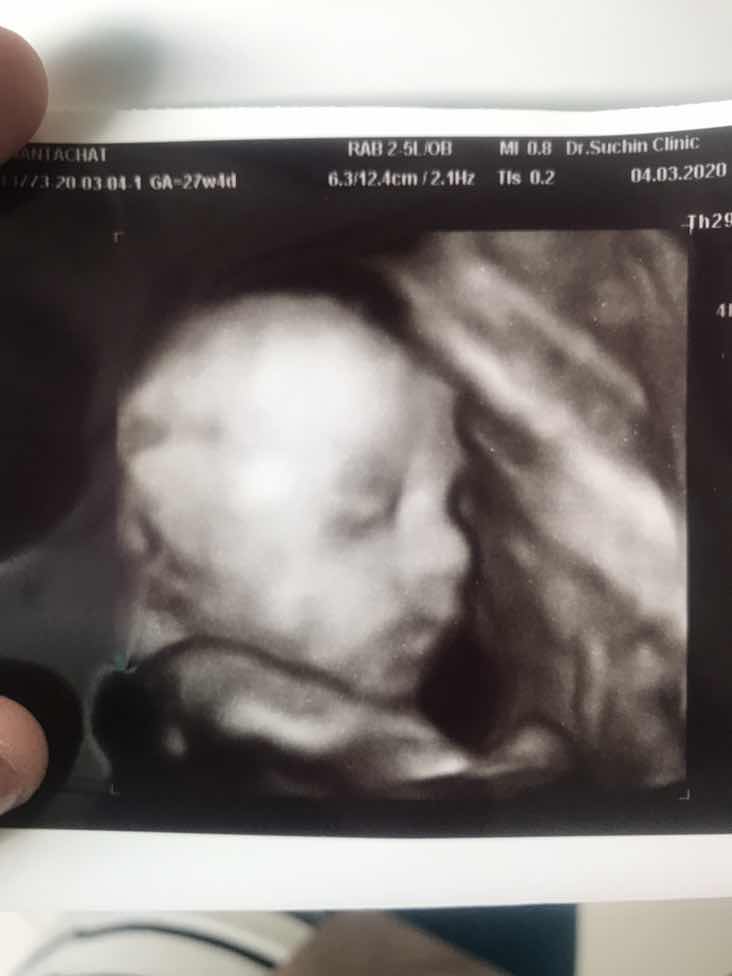

26w ค่ะ